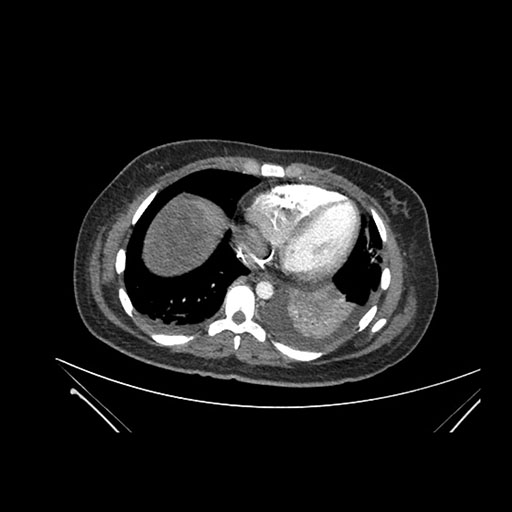

Axial Arterial